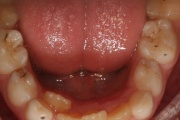

Suulaepoolt lõikunud koonilise kujuga lisahammas